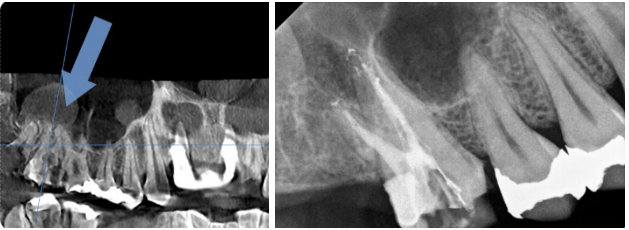

검사 결과, 오른쪽 치아의 치수강은 비교적 깨끗했지만, 왼쪽 치아는 내부 오염이 심한 상태였습니다.

치수강 오염이 심한 경우, 충치가 치아 뿌리 깊숙이까지 퍼졌을 가능성이 높아집니다. 이러한 상황에서는 치료를 성공적으로 진행하더라도 치아의 수명이 길지 않은 경우가 많습니다.

왼쪽 치아의 CT 검사 결과, 뿌리 아래쪽에 큰 염증이 확인되었습니다. 환자분께 치료 상황과 예후를 상세히 설명드린 후, 치아 보존이 어려울 가능성이 높아 발치를 원하셨고, 이후 임플란트를 진행하기로 결정했습니다.

반면 오른쪽 치아는 신경치료를 통해 치료를 마무리하였습니다.